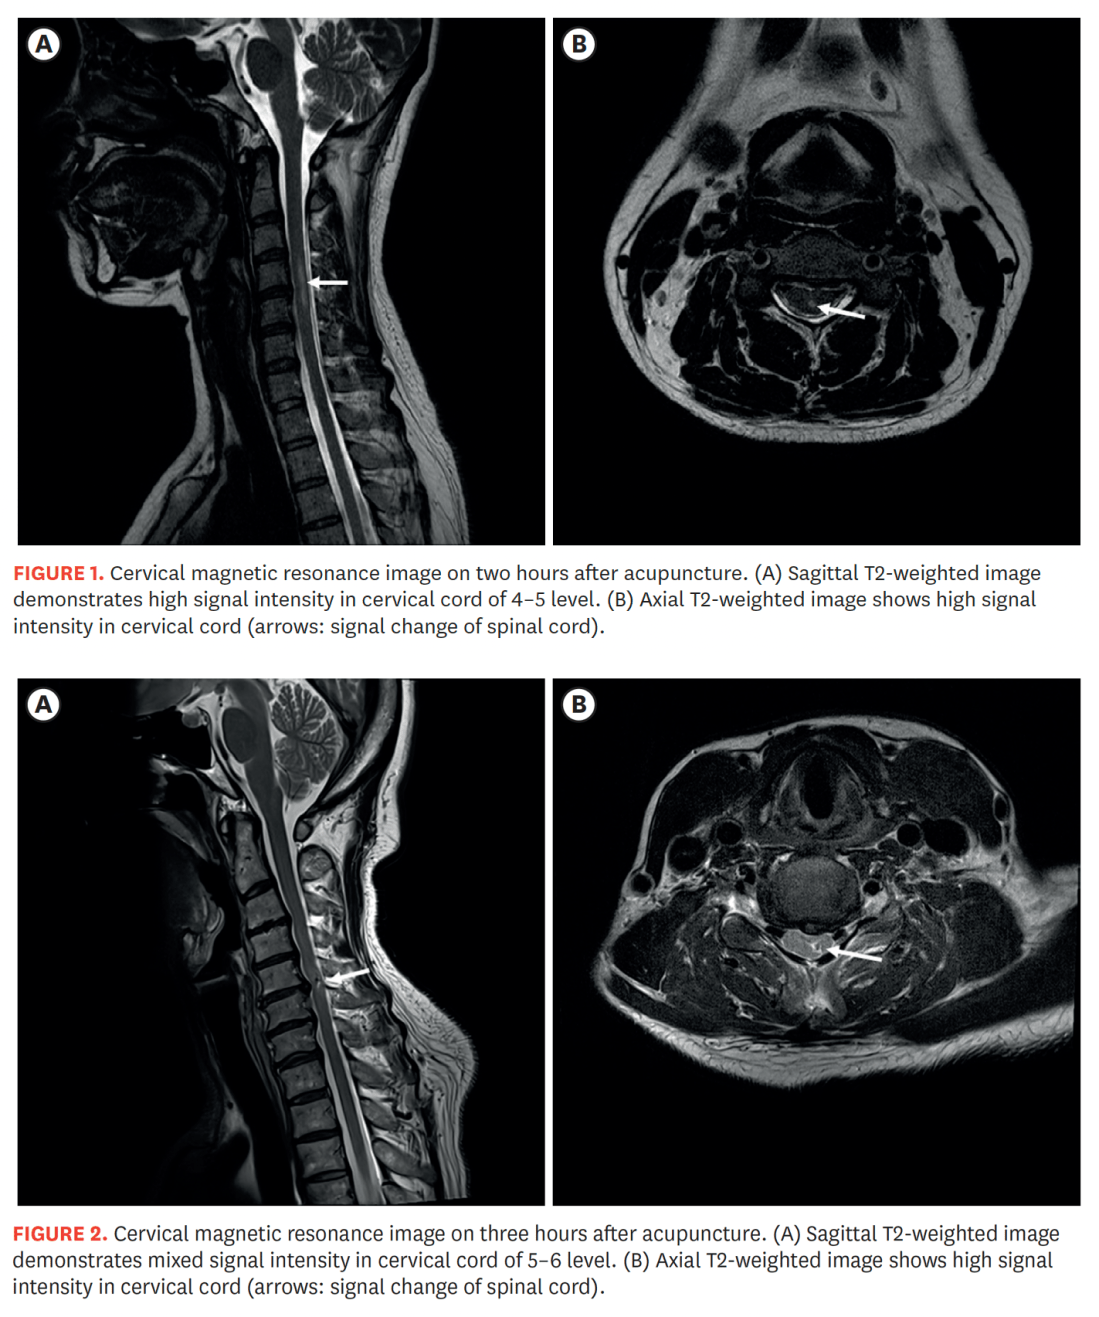

Needling necks and SCI 2025

Stimulated by Kim et al 2025.[1] SCI – spinal cord injury – key to acronym This paper was published in late August this year in the Korean Journal of Neurotrauma, but it has only just come up on my PubMed searches in the last week or so. It is not really extensive enough to devote … Continue reading Needling necks and SCI 2025